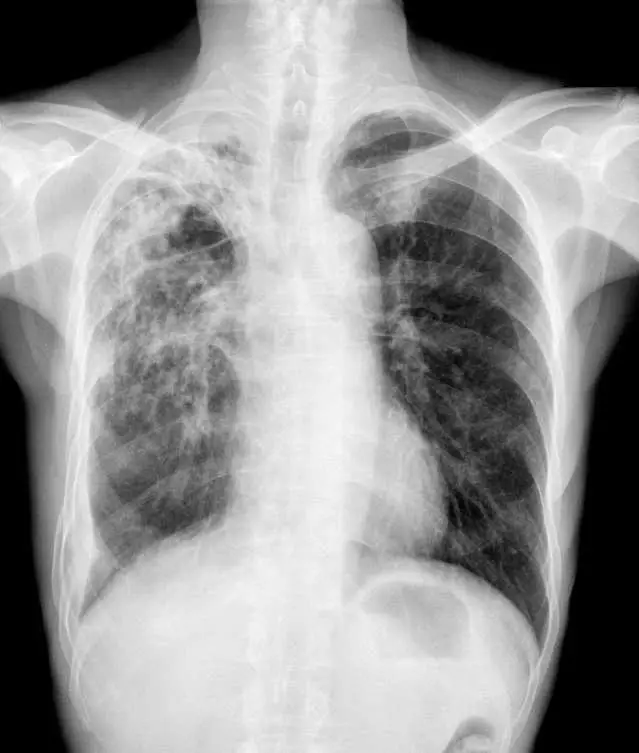

胸部 X 光(正面,PA view)顯示以下關鍵發現:

- 雙側瀰漫性粟粒狀結節(bilateral diffuse miliary nodules):兩側肺野均可見無數細小(1-3 mm)均勻散佈的結節影,密度均一,佈滿全肺,形如小米粒(millet seeds)——此為「粟粒型結核病」命名由來

- 分佈:從上肺到下肺均勻分佈,無明顯節段性偏好

- 心臟輪廓:大小正常

- 肋膜腔:無明顯積液

- 縱膈:未見明顯腫大淋巴結(但粟粒型 TB 可能有輕微縱膈變化)

此影像高度符合粟粒性肺結核(miliary pulmonary tuberculosis)——因結核菌菌血症(大量淋巴血行性播散)造成全肺瀰漫性播種,形成直徑約 1-5 mm 的均勻粟粒狀結節。臨床上結合 10 個月咳嗽、體